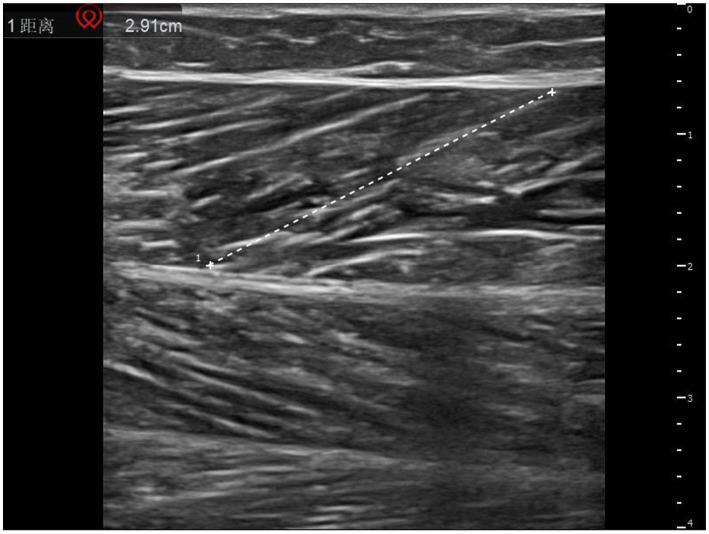

METHODS

A cross-sectional study was used to enroll 80 stroke patients admitted to the Rehabilitation Center of the Affiliated Hospital of Shandong University of Traditional Chinese Medicine from October 2024 to April 2025. The degree of lower limb spasticity was evaluated by the modified Ashworth Scale (MAS), and the proprioceptive assessment module of the Pro-kin balance system was used to quantitatively detect the mean trajectory error (ATE) and the average weight-bearing asymmetry (AWA). Musculoskeletal ultrasound was used to detect the spasmodic side and the healthy gastrocnemius muscle, and the longitudinal and transverse ultrasound images were obtained, and the length of muscle fibers, medial head pinnate angle and muscle thickness were measured. Spearman correlation analysis was used to explore the correlation between MAS score and various parameters, a multiple linear regression model was constructed to analyze the influencing factors of spasticity, and the predictive performance of ultrasound parameters was evaluated by receiver operating characteristic (ROC) curve.

方法

采用横断面研究方法,选取2024年10月至2025年4月在山东中医药大学附属医院康复中心收治的80例脑卒中患者。采用改良Ashworth量表(MAS)评估下肢痉挛程度,使用Pro-kin平衡系统的本体感觉评估模块定量检测平均轨迹误差(ATE)和平均负重不对称性(AWA)。采用肌肉骨骼超声检测痉挛侧和健侧腓肠肌,获取纵、横超声图像,测量肌纤维长度、内侧头羽状角和肌肉厚度。采用Spearman相关性分析探讨MAS评分与各参数之间的相关性,构建多元线性回归模型分析痉挛的影响因素,并通过受试者工作特征(ROC)曲线评估超声参数的预测性能。